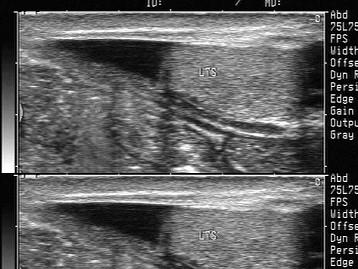

问题 男性,阴囊肿大,于右侧腹股沟见一混杂回声光团,探头压可回纳腹腔。如图所示,考虑为 ?(?)

选项 A.隐睾 B.腹股沟斜疝 C.精原细胞瘤 D.睾丸脓肿 E.以上都不是

答案 B